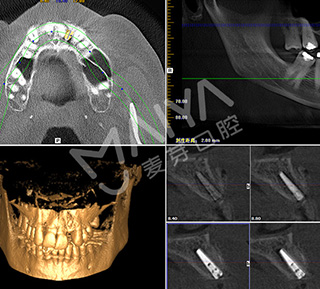

深圳市二院原口腔科主任、深圳麦芽口腔总院长、深圳科技进步一等奖获得者郑苍尚教授在仔细检查Jack的牙齿情况后,通过科学的德国卡瓦数字化口腔CT三维检测,指出Jack因为牙外伤后而导致牙反复发炎松动,牙CT显示牙槽骨严重缺损,不能一期种牙。